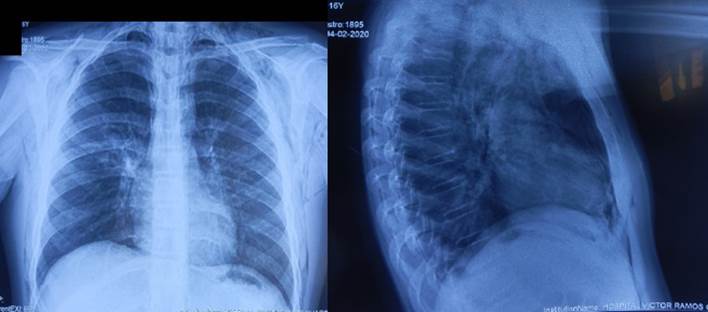

En el examen clínico se registra PA: 80/50 mmHg, FC: 138/min, FR: 37/min, temperatura: 37,1 ºC, saturación de oxígeno: 78 % al aire ambiental que llega a 87 % con FiO₂: 36 %. El paciente es un varón adolescente que ingresa en camilla con oxígeno nasal, alerta, ansioso, polipneico, ventila espontáneamente, afebril. Se palpa enfisema subcutáneo, crepitación en ambos lados del cuello y del tórax anterior. Sus pulmones se presentan crepitantes y difusos. El sistema cardiovascular se ve afectado por ruidos cardíacos aumentados en frecuencia e intensidad, no hay soplos. En el resto del examen no hay hallazgos de importancia (Figura 2). Se le administró oxígeno por cánula nasal, y se indicó analgesia y ceftriaxone. Se observó gran mejoría y el paciente solicitó su retiro voluntario el 23 de febrero del 2020.

En la radiografía frontal y lateral con la cánula nasal de oxígeno se ven sombras lineales a lo largo de los márgenes mediastínicos y presencia de aire retroesternal. También aparecen imágenes radiolúcidas irregulares en tejidos blandos del cuello y tórax derecho, que sugieren enfisema subcutáneo. Impresiona un leve infiltrado alveolar irregular parahiliar derecho (Figura 2).

Figura 2 Neumomediastino y enfisema subcutáneo.